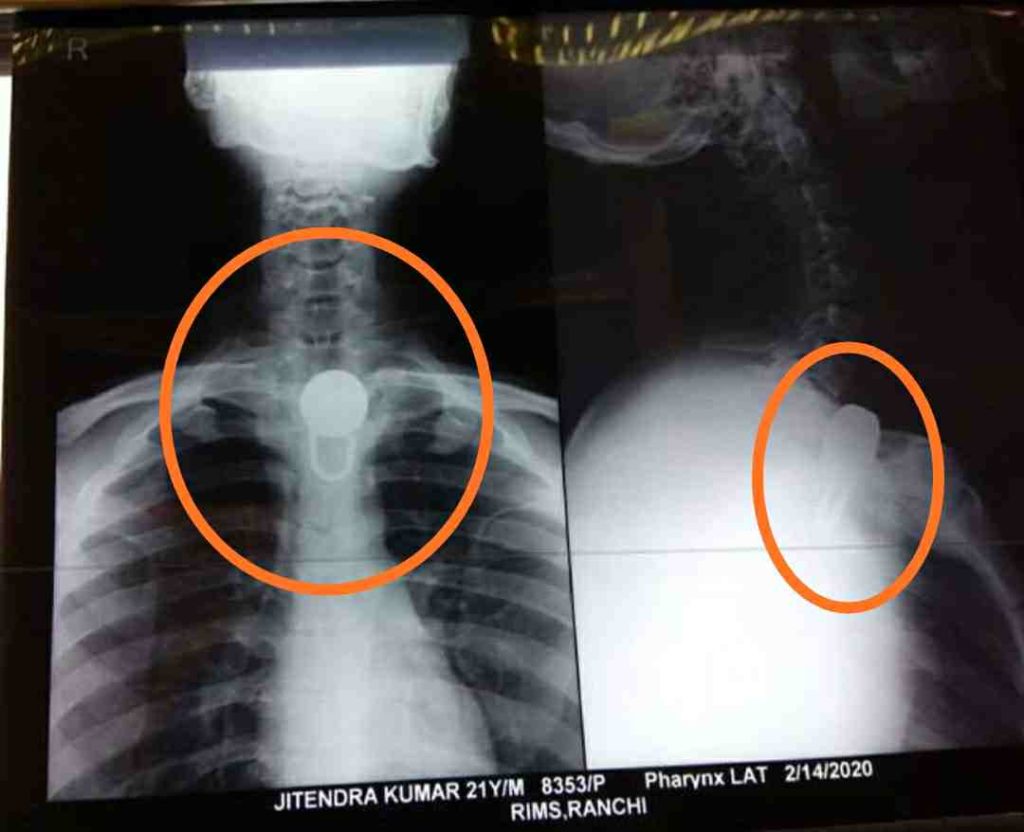

AJ डेस्क: रांची के रिम्स के ईएनटी विभाग में गुरुवार को गले के नीचे ताला फंसे मरीज की गर्दन खोलकर जटिल सर्जरी की गई। ईएनटी के एचओडी डॉ. पीके सिंह की यूनिट के एसोसिएट प्रो. डॉ. जाहिद खान के नेतृत्व में सर्जरी हुई। डॉ. जाहिद खान ने बताया कि 23 साल का मरीज कोडरमा का रहने वाला है। बीते शुक्रवार को मरीज को रिम्स में भर्ती किया गया। एक्सरे से पता चला कि मरीज के गले के नीचे खाने के रास्ते में बड़े आकार का ताला फंसा है।

ऑपरेशन के बाद डॉ. जाहिद ने बताया कि ताला का आकार बड़ा होने के कारण बगैर गर्दन खोले निकालना संभव नहीं था। ऑपरेशन में डॉ. जाहिद खान, डॉ. संगीता, डॉ. निभा, डॉ. रागिनी, एनेस्थीसिया से डॉ. खन्ना व डॉ. शालिनी शामिल थे। डॉ. जाहिद ने बताया कि मरीज मनोरोगी है। घर में उसे ताला व सिक्कड़ से बांध कर रखा जाता था।

उसने खुद में लगे ताले को किसी तरह से खोलकर निगल लिया, जिसके बाद वह खाने की नली में जाकर अटक गया। रिम्स के ईएनटी विभाग में भर्ती इस मरीज को नर्सो की स्पेशल केयर में रखा गया है। मरीज खुद से कोई खाद्य पदार्थ का सेवन न करें इसके लगातार नजर रखने का निर्देश भी दिया गया है।